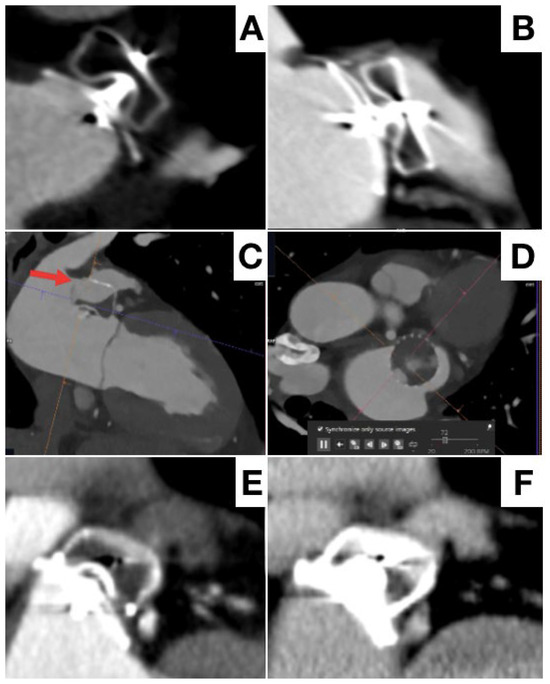

- Korsholm, K.; Jensen, J.M.; Nørgaard, B.L.; Nielsen-Kudsk, J.E. Detection of Device-Related Thrombosis Following Left Atrial Appendage Occlusion: A Comparison Between Cardiac Computed Tomography and Transesophageal Echocardiography. Circ. Cardiovasc. Interv. 2019, 12, e008112. [Google Scholar] [CrossRef] [PubMed]

- Korsholm, K.; Jensen, J.M.; Nørgaard, B.L.; Samaras, A.; Saw, J.; Berti, S.; Tzikas, A.; Nielsen-Kudsk, J.E. Peridevice Leak Following Amplatzer Left Atrial Appendage Occlusion: Cardiac Computed Tomography Classification and Clinical Outcomes. JACC Cardiovasc. Interv. 2021, 14, 83–93. [Google Scholar] [CrossRef]